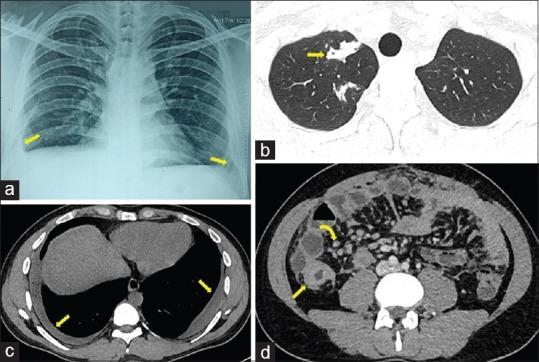

Tuberculosis is a well-known entity in India with many implemented policies to ensure the cost-effective early management. Missed, delayed, and complicated presentations do occur, requiring expensive tertiary level of health care. Among many contributing factors, lack of antibiotic stewardship is at the top. We report a case of 65-year-old man who presented with on and off fever for six months, receiving cocktail treatments of antibiotics, analgesics, and steroids from a local dispensary. Our initial investigations revealed microcytic anemia with high erythrocyte sedimentation rate, leukocytosis, and bilateral pleural effusion on chest X-ray. Contrast enhanced computer tomography of chest and abdomen suggested disseminated tuberculosis including bilateral empyema. Frank pus was drained on thoracocentesis, which was negative for Gram stain, Ziehl-Neelsen stain, and bacterial culture, but positive CB-NAAT for tubercular bacilli with no resistance to rifampicin. Mantoux test and stool occult blood were positive. This case highlights an unusual presentation of tuberculosis and the ongoing lacunae in the society with importance to the primary care providers in the effective management of tuberculosis focusing on antimicrobial stewardship.